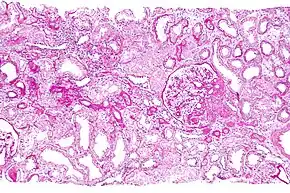

Micrograph showing a renal core biopsy. PAS stain. | |